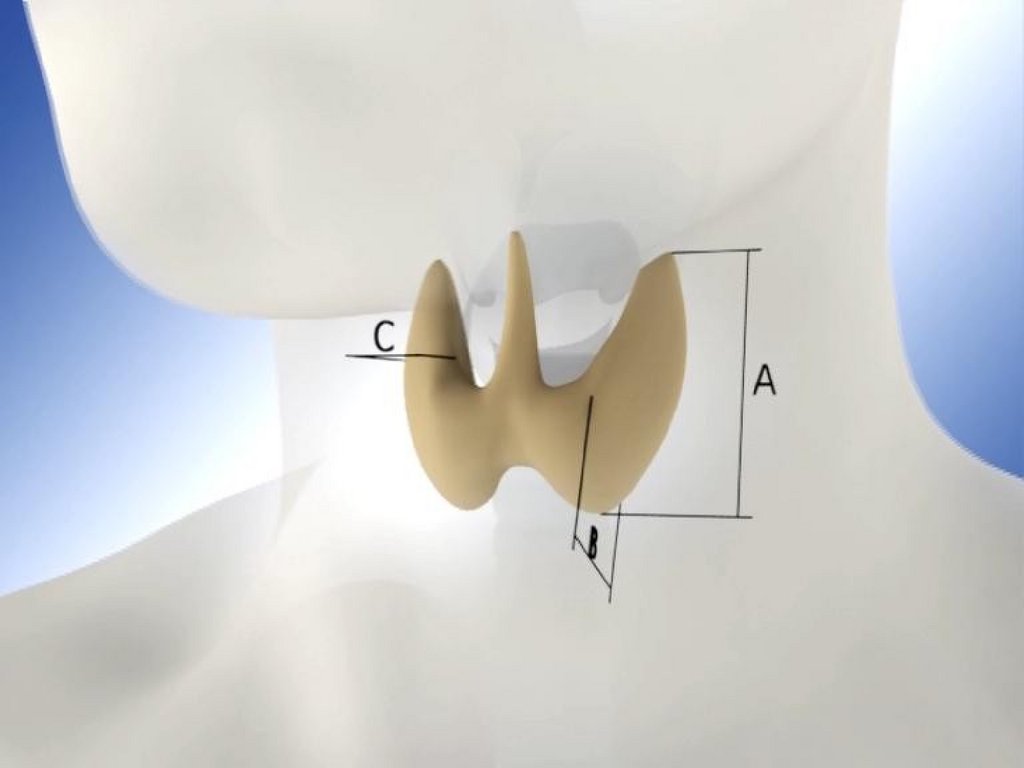

Диагностика зоба при помощи

ультразвукового исследования

B

А

Для расчета объема ЩЖ складываются

объемы двух долей; размером перешейка

пренебрегают

C

Пациенты

Нормальный объем ЩЖ (мл)

Дети 6 – 10 лет

<8

Дети 11 – 14 лет

< 10

15 – 18 лет

< 15

Женщины

< 18

Мужчины

< 25

24